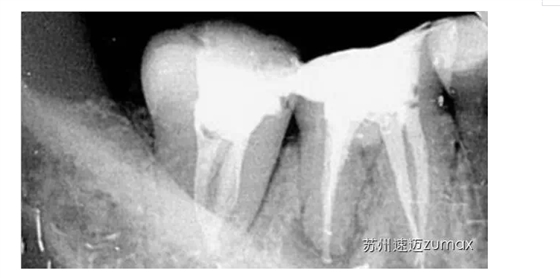

C形根管的治療最好是在手術(shù)顯微鏡下進行。上橡皮障后開髓,去除髓室中的牙髓組織,使用DG16仔細探查根管口位置,然后用10或15號不銹鋼K銼探查根管的形態(tài)、直徑和走向。當根管口呈連續(xù)的C形時,插入根管內(nèi)的診斷銼為2~4個,通常為3個。當根管口呈分號形時,可以在較小的根管內(nèi)插入1個診斷銼,在較大的根管內(nèi)插入1~3個診斷銼。